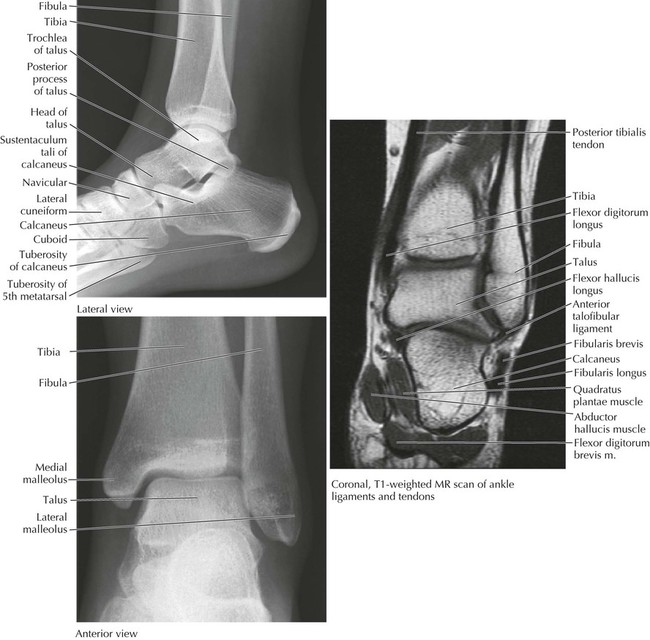

The ankle connects the foot to the leg and is composed of seven tarsal bones arranged in a proximal group (talus and calcaneus), intermediate group (navicular), and distal group (cuboid and three cuneiforms). The foot includes five metatarsals and the five digits and their phalanges (Figs. 6-25 and 6-26 and Table 6-18).

The ankle (talocrural) joint is a uniaxial synovial hinge joint between the talus and the tibia (inferior surface and medial malleolus) and fibula (lateral malleolus). This combination forms a mortise that is then covered by the capsule of the joint and reinforced medially and laterally by ligaments. The ankle joint functions primarily in plantarflexion and dorsiflexion. Intertarsal, tarsometatarsal, intermetatarsal, metatarsophalangeal, and interphalangeal joints complete the ankle and foot joint complex (Fig. 6-27 and Table 6-19). A variety of movements are possible at these joints, and the ankle and foot can provide a stable but flexible platform for standing, walking, and running. Because of the shape of the talus (the anterior portion of its superior articular aspect is wider), the ankle is more stable when dorsiflexed than when plantarflexed.